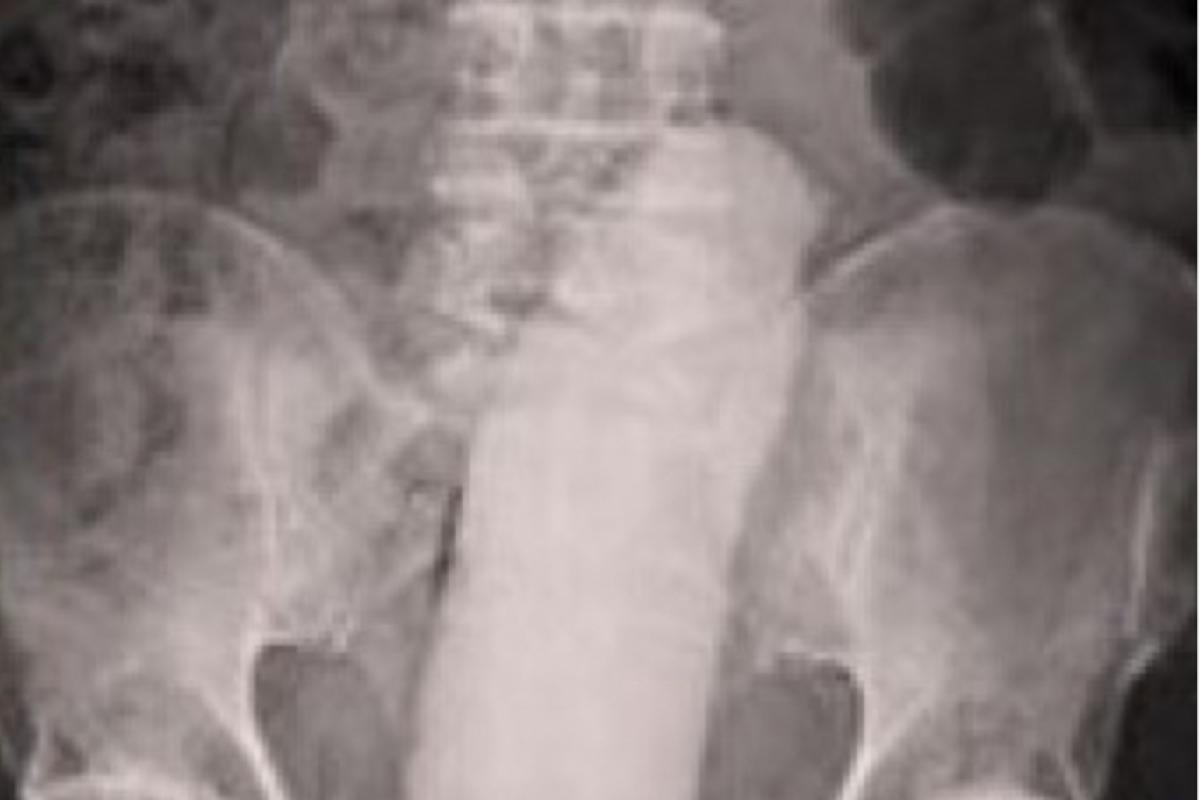

Um homem que precisou ser internado às pressas para a retirada de um objeto introduzido no ânus, desapareceu misteriosamente no último sábado (21), após o procedimento cirúrgico no Hospital Vale do Guaporé, em Pontes e Lacerda (a 450 km de Cuiabá).

Segundo informações, o paciente foi atendido em caráter de emergência e encaminhado diretamente para a cirurgia. No entanto, por volta das 17h45, a equipe médica percebeu que o homem havia desaparecido do hospital, levando consigo todos seus pertences.

A direção da instituição não divulgou detalhes sobre o estado de saúde do paciente e o tipo de objeto que estava dentro do homem.